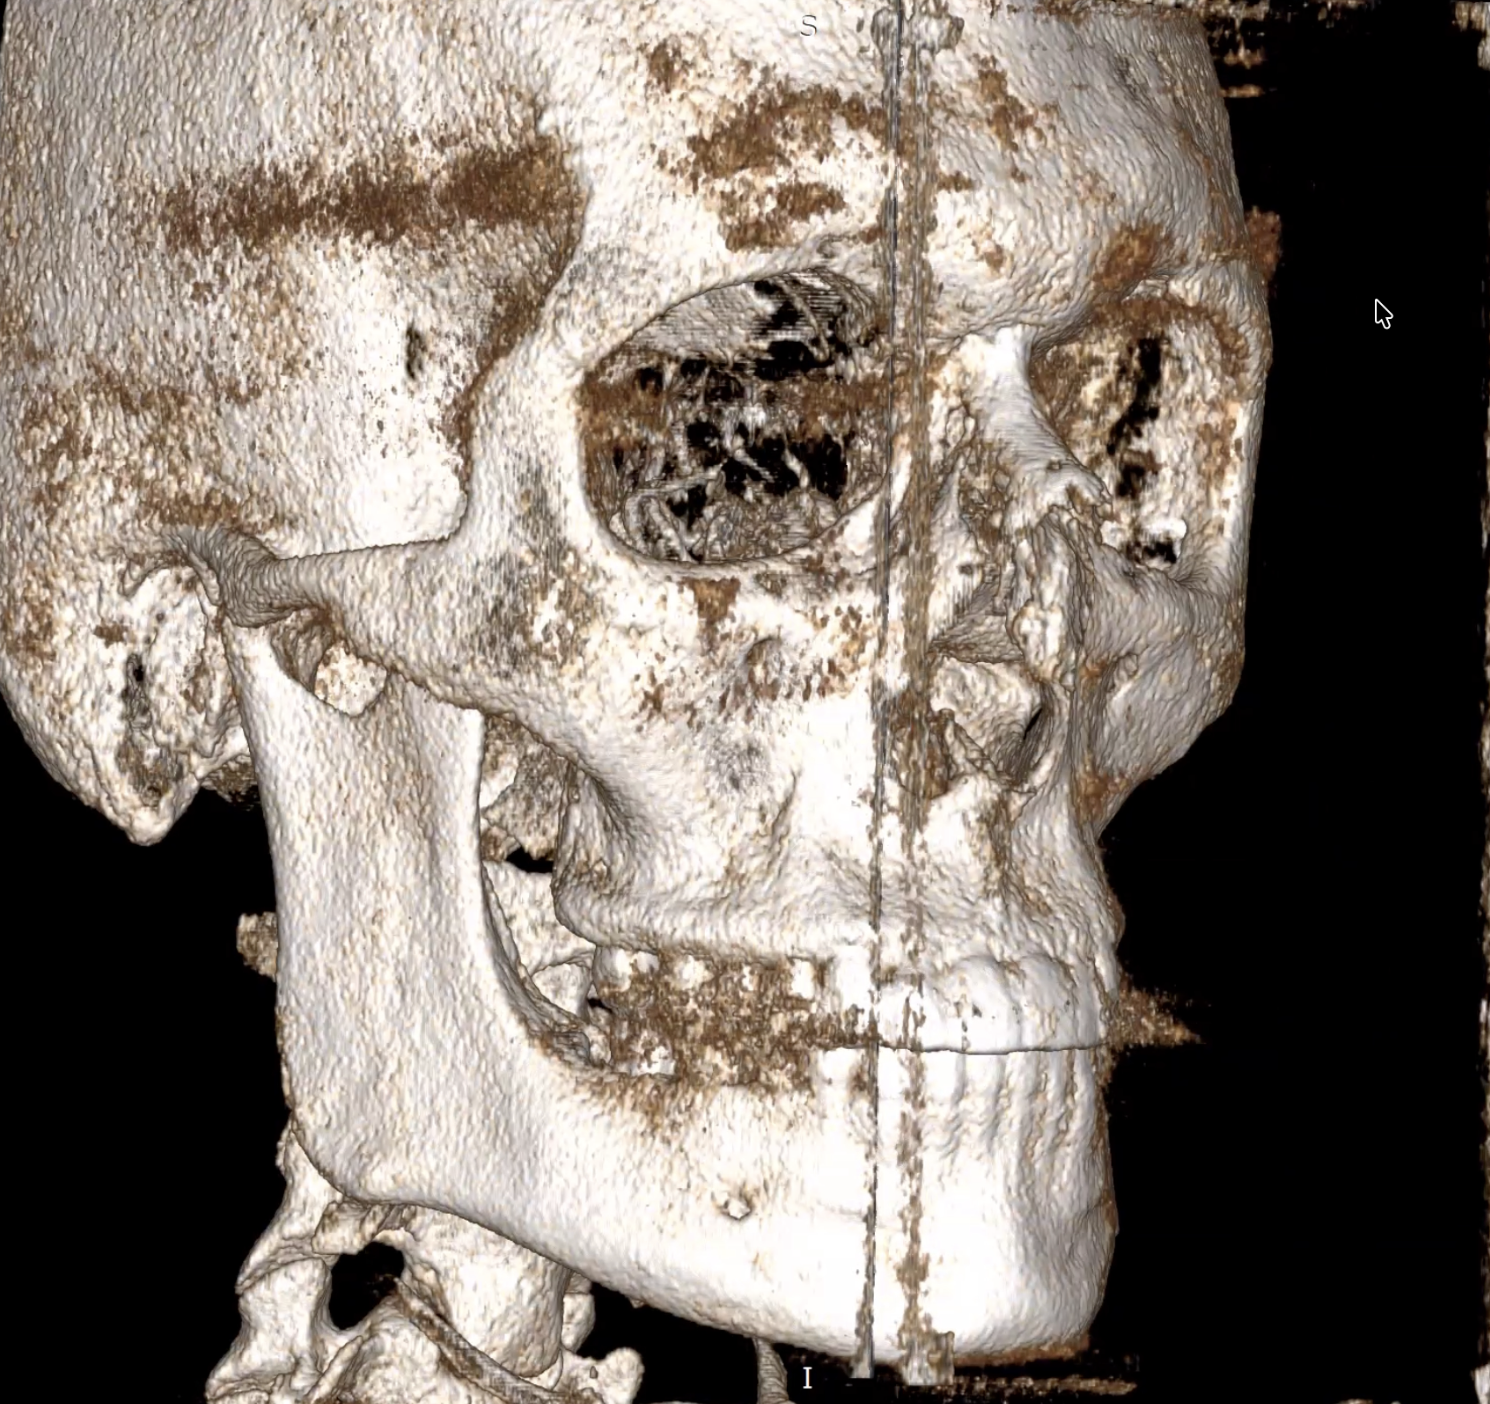

So we get on the video call, he pulls up my CBCT, and the first thing he does is look at the oblique view and says he doesn't see anything substantial. I'm sitting there like ok maybe it's worse in lateral. He goes to the lateral view. Says the zygomatic area might look slightly flat but considers it normal anatomy. Not pathological. Not even really a problem.

Then he drops something I genuinely hadn't considered before. He points out my frontal sinus is hyperpneumatized, basically my brow ridge is very pronounced, and he explains that this actually shifts the visual reference line of the face forward. So when you look at the profile, the brow ridge sticks out so much that it makes everything below it LOOK more recessed than it actually is. He says if you take the nasion as the correct reference point, everything is fundamentally aligned. The recession I've been obsessing over for a year might be partially an optical illusion created by my own brow ridge.

So we get on the video call, he pulls up my CBCT, and the first thing he does is look at the oblique view and says he doesn't see anything substantial. I'm sitting there like ok maybe it's worse in lateral. He goes to the lateral view. Says the zygomatic area might look slightly flat but considers it normal anatomy. Not pathological. Not even really a problem.

Then he drops something I genuinely hadn't considered before. He points out my frontal sinus is hyperpneumatized, basically my brow ridge is very pronounced, and he explains that this actually shifts the visual reference line of the face forward. So when you look at the profile, the brow ridge sticks out so much that it makes everything below it LOOK more recessed than it actually is. He says if you take the nasion as the correct reference point, everything is fundamentally aligned. The recession I've been obsessing over for a year might be partially an optical illusion created by my own brow ridge.